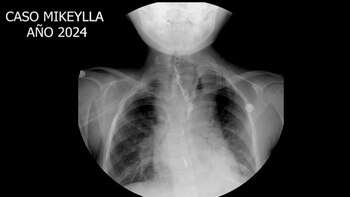

Mikeylla, una niña de nueve años, ha recuperado la posibilidad de llevar una vida normal gracias a una compleja cirugía realizada en el Hospital Nacional Edgardo Rebagliati Martins de EsSalud.

Desde su nacimiento, había dependido de una sonda para alimentarse debido a una condición congénita conocida como atresia esofágica tipo III, que impedía el desarrollo completo de su esófago. Esta malformación le impedía ingerir alimentos de manera natural, lo que afectaba su crecimiento y desarrollo.

La técnica utilizada, conocida como ascenso gástrico, consistió en extirpar los remanentes del esófago y elevar el estómago a la altura del tórax. De esa manera, se crea un conducto que permite la comunicación con la boca.

Este procedimiento permitirá que la menor, quien hasta ahora dependía de una gastrostomía para comer, pueda ingerir alimentos sólidos y llevar una vida sin las limitaciones que había enfrentado.